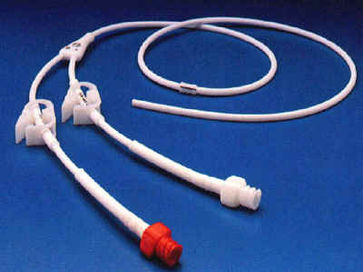

-Tunnelierte Katheter einlumig dünn aus Silikon für TPN, mehrlumig dick aus Silikon für Apherese, Dialyse und Knochenmarkstransplantation.

-Ports für gelegentliche Anwendung über langen Zeitraum (Chemotherapie).

Tunnelierung und Port

Langzeitkatheter und Portkatheter werden von der Punktionsstelle supraklavikulär 4 - 6 cm bis zum Thorax tunneliert.

Da tunnelierte Katheter eine fixe Länge haben, muß die Austrittsstelle exakt vermessen werden, dass einerseits die Katheterspitze im Vorhof bzw. der Vena cava superior liegt, andererseits der Tefloncuff mindestens 2 cm von der Austrittsstelle entfernt im Tunnel.

Portkammern sollen im Trigonum deltoideo-pectorale (Mohrenheim´sche Grube) liegen, bei Frauen ist darauf zu achten, dass sie nicht unter dem BH-Träger liegen und keinesfalls auf dem Brustansatz.

-Niemals Blutabnahme aus einem Port oder tunnelierten Katheter. Jede Blutabnahme führt zu einer gesetzmäßien Ereigniskaskade, an deren Ende der Verlust des Katheters und oft auch des Patienten steht. Bei Blutkontakt entsteht auf dem Kathetermaterial ein Biofilm (Fibrin und Fibronectin). Adhärenz von Bakterien und Thrombozyten am Fibronectin. Thrombozytenaktivierung, Leukozytendegranulation, Komplementaktivierung, Gerinnungsaktivierung. Bildung einer Fibrinmanschette um den Katheter und eines Thrombus im Katheter sowie Sepsis durch die adhärenten Bakterien. Bei nicht tunnelierten Kathetern ist die Blutabnahme nicht so dramatisch, sofern diese ordnungsgemäß alle 5 Tage gewechselt werden.

-Bei Kathetern, die zum Zweck der Blutabnahme implantiert wurden( Apherese, Dialyse) kann dieser Ablauf durch intensive Spülung und Instillation von 1 mg Actilyse nach jeder Benutzung verzögert werden.

-Ports und nicht benutzte Katheter müssen mit einer Heparinplombe gefüllt werden.